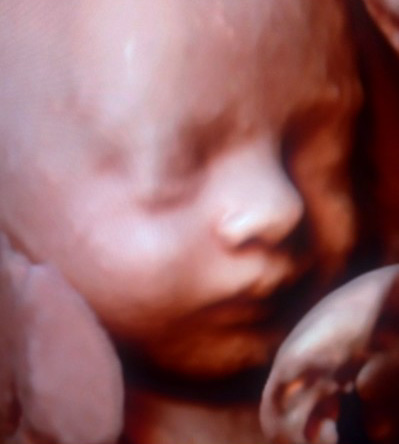

Az 5D ultrahang már a 4D ultrahang továbbfejlesztett változata, mely még élethűbb képet ad a méhen belüli magzatról, így egy igazi moziélményben, felejthetetlen emlékben lehet részük! A szülők olyan szemmel láthatják babájukat, mintha ők maguk is az anyaméhben lennének.

Az 5D Babamozi lehetőséget ad a szülőknek, hogy közelebb kerüljenek a magzathoz, megtapasztalják a terhesség csodáját, nyomon kövessék hogyan fejlődik a gyermekük az anyaméhben.

Természetesen minden terhességi korban más és más a vizuális élmény. Fontos tudni, hogy a felvétel láthatóságát nagyban meghatározza a baba fekvése, ébrenléti állapota is. De ha azt szeretné tudni, az 5D Babamozit mikor érdemes elvégeztetni, nos a várandósság 24-32 hete között ajánlom a legnagyobb élvezhetőség érdekében.